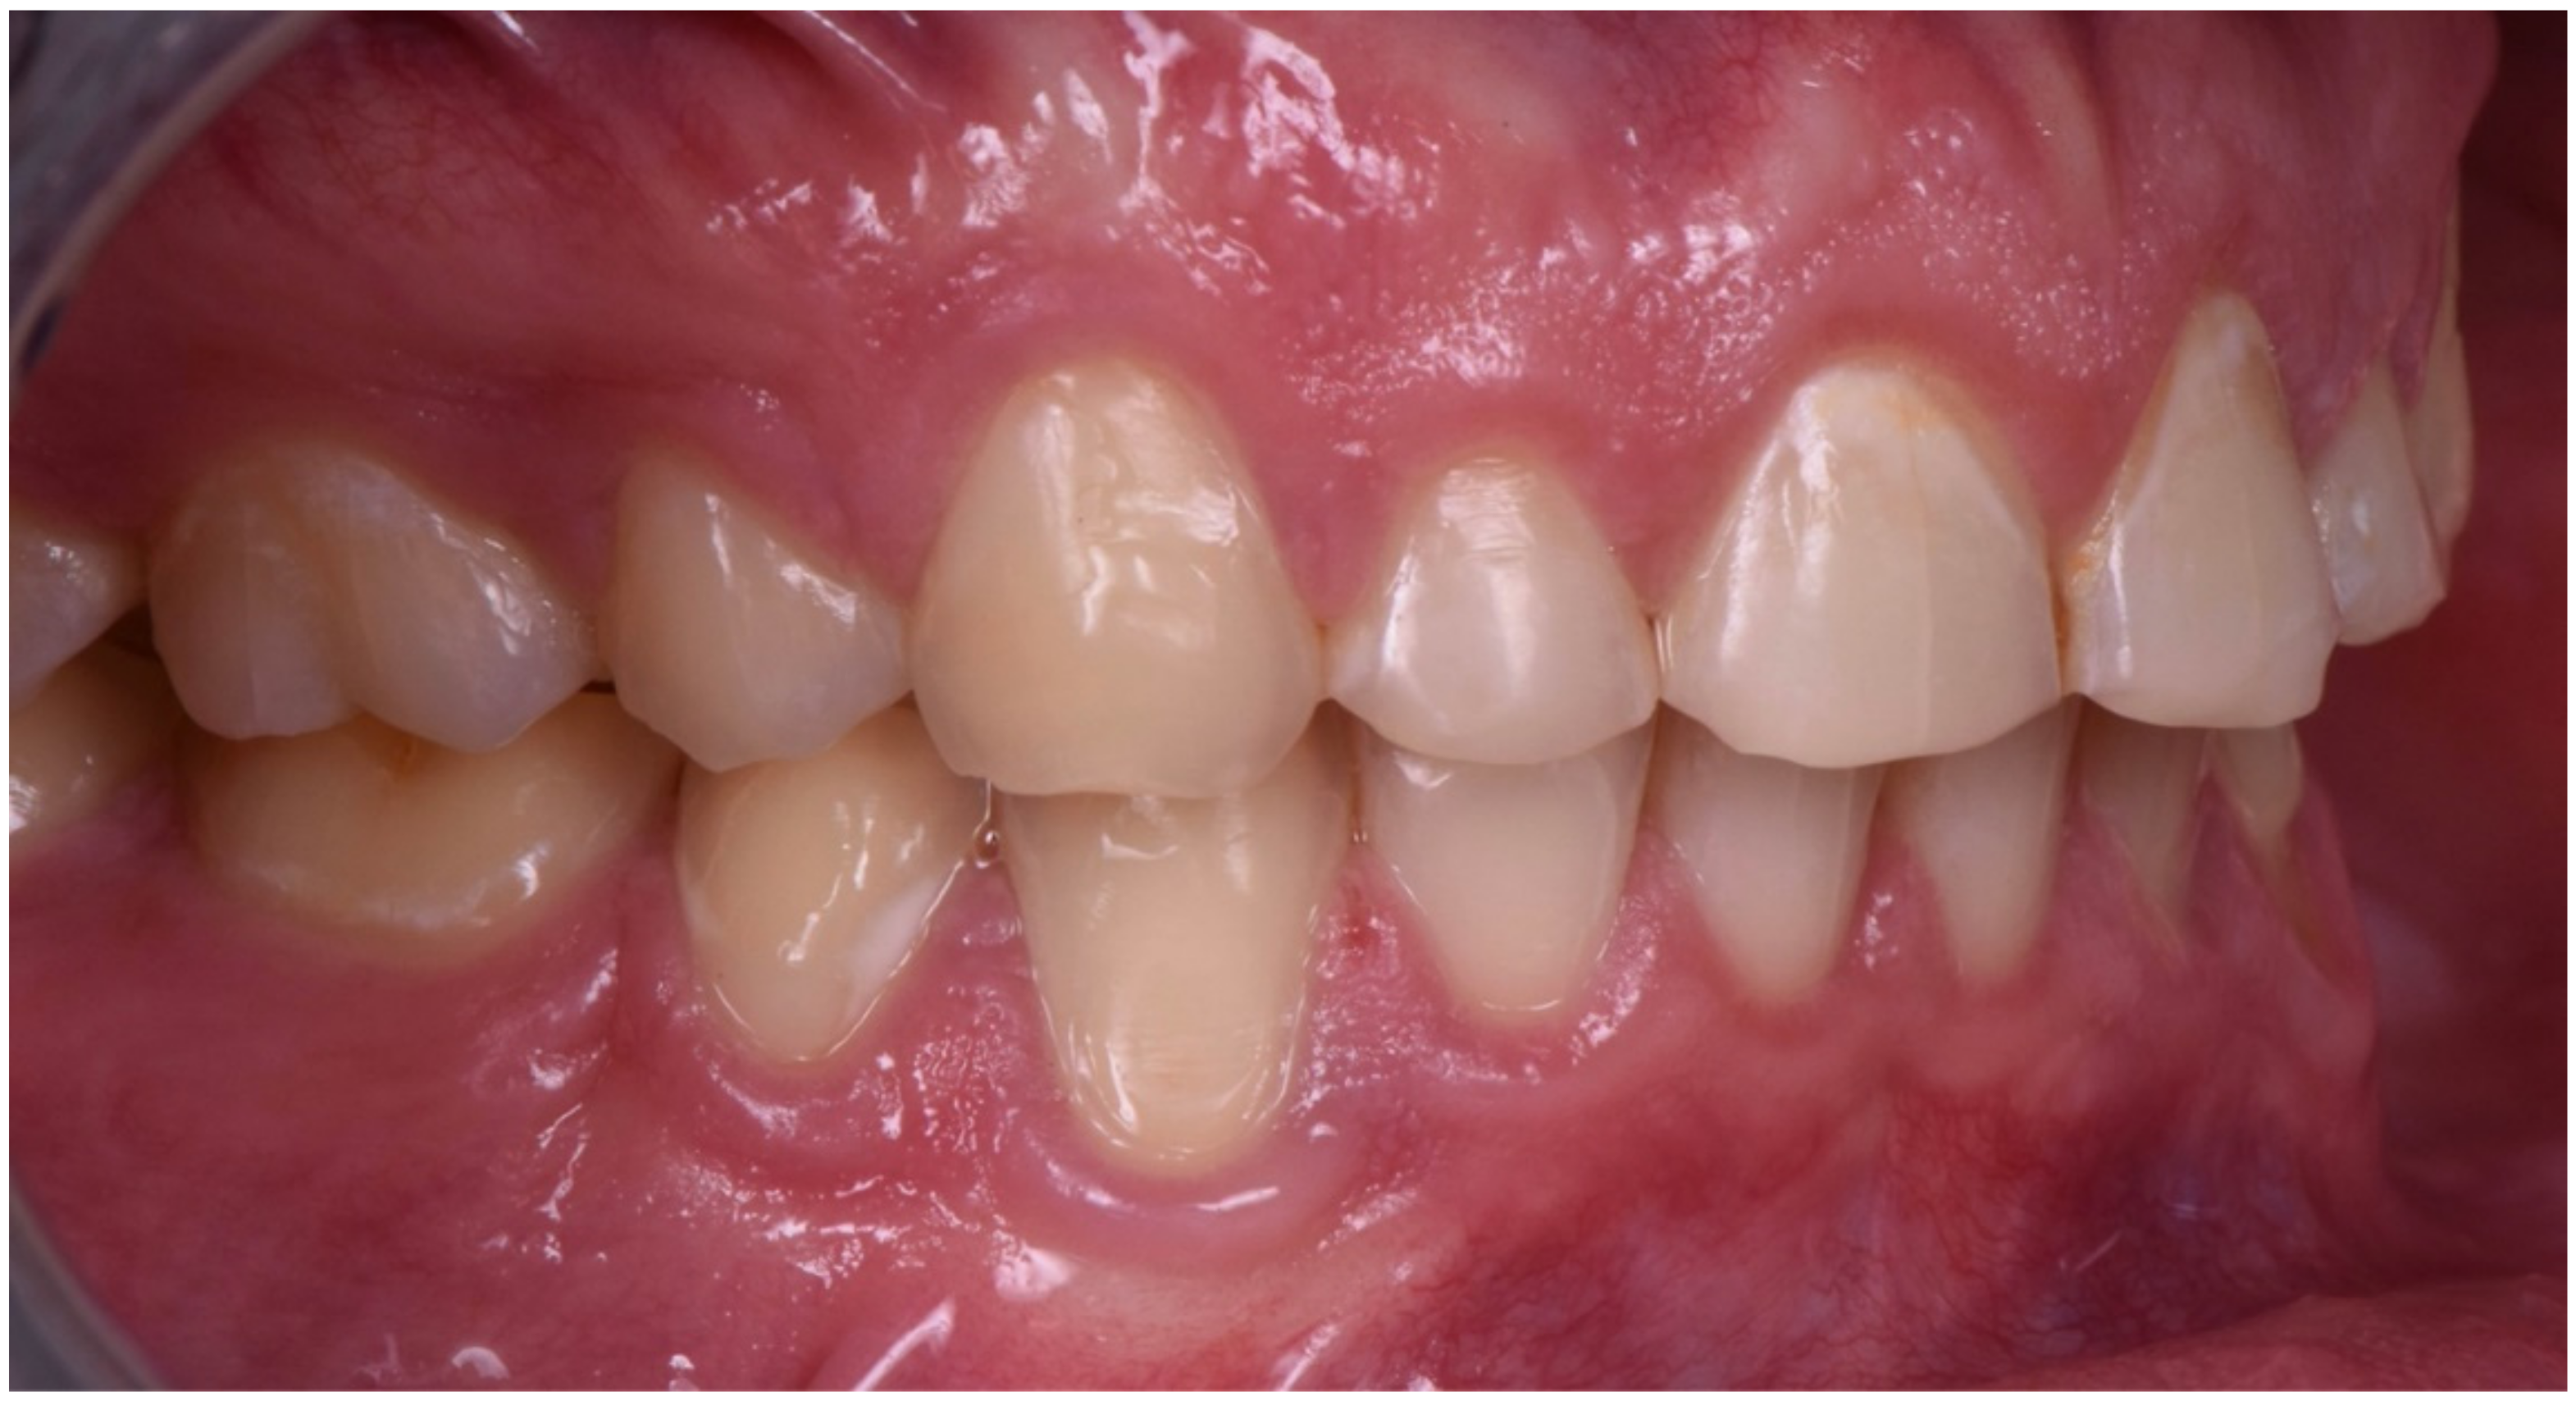

2. Clinical Report